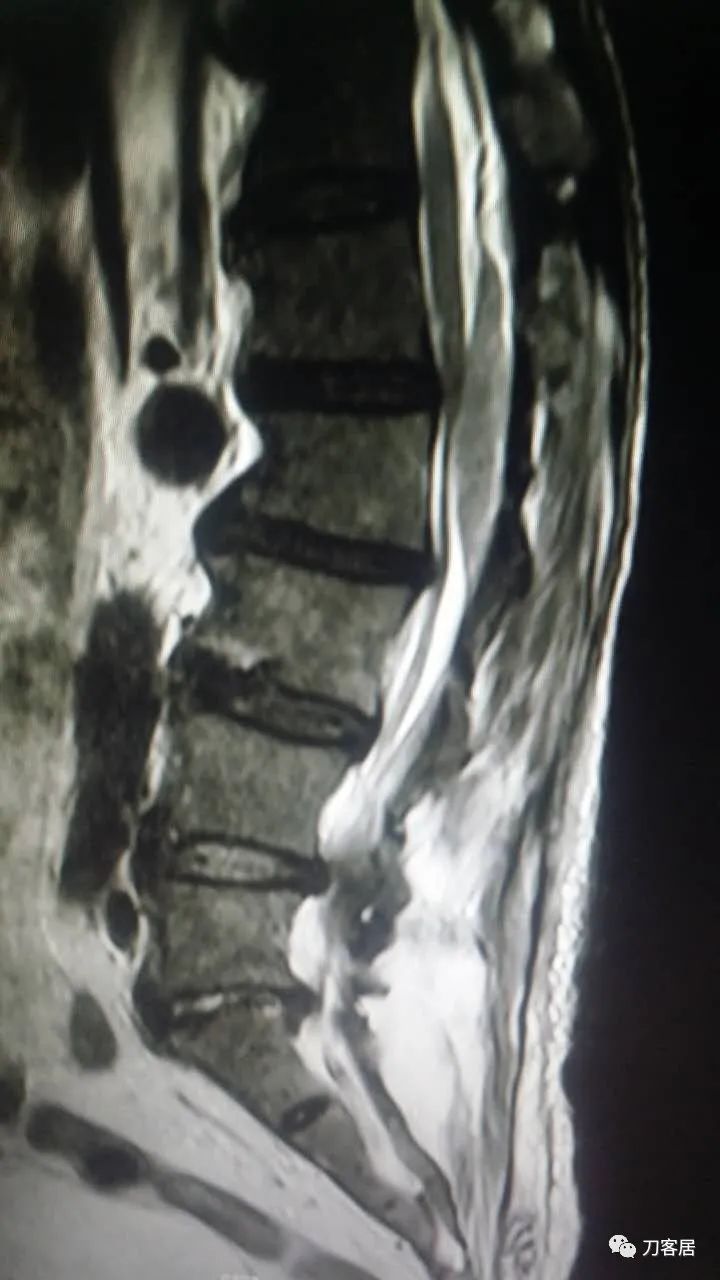

加注图4. 2015年8月17日术后5天,复查腰椎MRI提示术后改变,此平面图并没有见椎管内异常改变。

加注图5. 2015年8月17日术后5天,复查腰椎MRI提示术后改变,此平面图现在看,似乎在腰1-3椎管后方有异常信号改变,但当时手机上看,咨询我的时候,我并没有看出来,这是在电脑上操作,放大图看,似乎这里还是有问题的,但腰4-5,腰5骶1平面,椎管内信号紊乱,应该是手术后的正常表现。

加注图6-加注图7. 腰4-5、腰5骶1平面,可见手术入路形成的减压窗口。椎管内无血肿压迫。

加注图10: 腰1-2椎管内后方可见梭形占位信号改变。

加注图11. 腰1-2椎管内后方可见梭形占位信号改变。

加注图12. 术前腰椎MRI,提示腰4-5,腰5骶1椎间盘突出,腰1-2椎管内无占位病变的信号。

加注图13. 术前腰椎MRI,提示腰4-5,腰5骶1椎间盘突出,腰1-2椎管内无占位病变的信号。